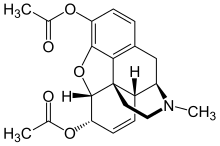

- Esters of morphine opiates: slightly chemically altered but more natural than the semi-synthetics, as most are morphine prodrugs, diacetylmorphine (morphine diacetate; heroin), nicomorphine (morphine dinicotinate), dipropanoylmorphine (morphine dipropionate), desomorphine, acetylpropionylmorphine, dibenzoylmorphine, diacetyldihydromorphine;[261][262]